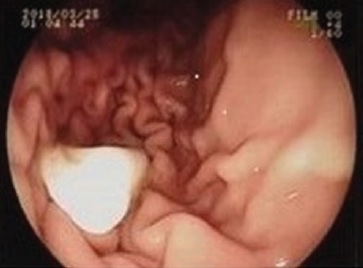

However, after a six-hour wait, a subsequent abdominal X-ray confirmed that the fecal material had passed into the intestine while the tooth remained lodged in the stomach mucosa. Thus, the doctor and the family agreed to proceed with a gastrointestinal endoscopy to retrieve the tooth (Figure 1).

Figure 1 Upper gastrointestinal endoscopy image (esophagogastroduodenoscopy) showing the tooth lodged in the stomach mucosa.

Gastrointestinal endoscopy was performed under deep sedation with propofol. The tooth was successfully recovered using tweezers and preserved in a saline solution. The patient recovered cognitive function after 15 minutes, and 10 minutes later, he arrived at the private dental office with his parents.